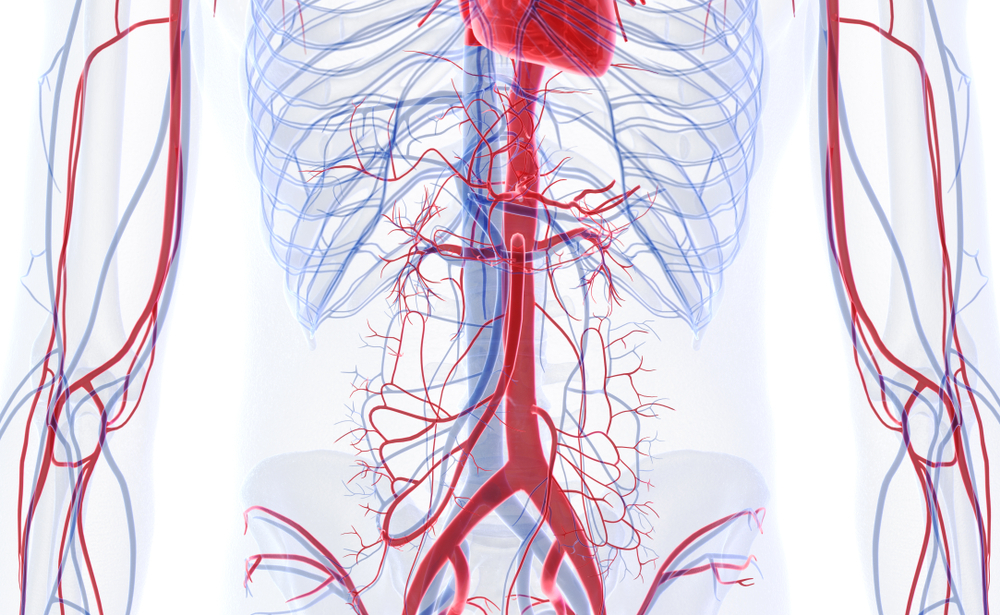

La CCL propose une offre chirurgicale complète — orthopédie, chirurgie générale, vasculaire et neurochirurgie — avec un suivi rigoureux et une équipe dédiée à votre rétablissement.